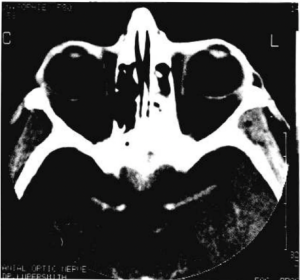

- Neuroimaging studies such as head and orbital CT and/or MRI with and without contrast [1]

Radiographic features vary depending on the etiology but generally, an intracranial mass causing optic nerve compression and resulting in features of optic atrophy can be seen.[3]